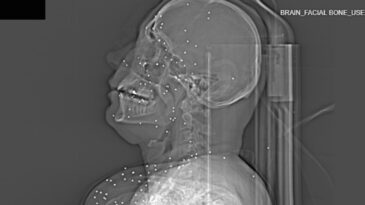

İran'da geçen ay artan rejim karşıtı protestolar sırasında güvenlik güçlerinin protestoculara uyguladığı şiddetin boyutunu gözler önüne seren yeni tıbbi ra...